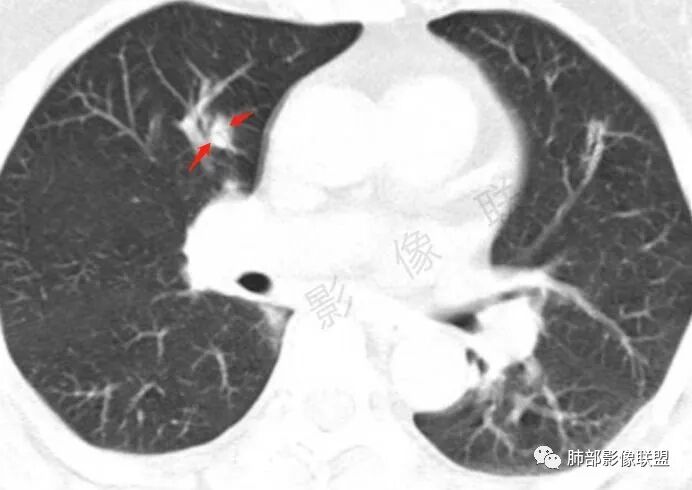

影像上:多发结节沿血管分布;双下叶支气管血管束简直增厚,偏血管,支气管通畅

膀胱炎症

肠系膜血管周围有渗出

左上颌窦粘膜下囊肿,鼻甲肥厚

右肾结石

首先肺部气道来源的病变不符合

因为支气管壁增厚,远端应该小气道病变,这个不是,反而是血管增粗明显

加上结节的分布,支持血管相关病变

累及范围广泛:肠系膜血管?膀胱